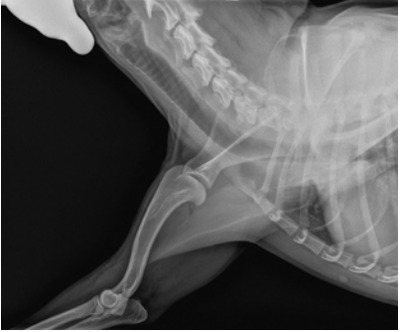

Патологии: - Прогрессирующая миоклоническая эпилепсия. - Грыжа в шейном отделе, сопровождающаяся тремором и толчками. - Дефицит бокового восприятия, особенно справа. - Дисплазия плеча, вызывающая воспаление нервов шейного отдела позвоночника. - Выраженная слабость суставов. - Цистит с потерей крови после течки. - Бронхиолит - Ложная беременность - Гиперхолестеринемия. - Guardian (вероятно препарат против клещей и блох-?): вызывает анафилактический шок. - Вакцинация: вызывает анафилактический шок. - История рецидивирующих отитов. ИСТОРИЯ БОЛЕЗНИ Июнь 2012 e-mail: «Добрый вечер, пишу вам, чтобы попросить консультацию... у моей собаки породы бигль уже несколько месяцев проблемы с грыжей шейного отдела позвоночника со множеством проблем. Симптоматика ухудшается, наблюдаются подергивания и шаткость походки, сейчас мы лечимся кортизоном, который не улучшает, а даже ухудшает общее состояние здоровья. Мы хотели бы получить ваше мнение и записаться на прием в вашу клинику. Мы пытаемся отменить кортизон, но вчера вечером у нее был приступ тремора и возбуждения, и мы дали таблетку 5 мг. Прошел месяц с начала приема кортизона через день по одной таблетке 5 мг один раз в день... мне сказали, что это низкая дозировка для собаки весом 15 кг, но я вижу, что если ей не давать лекарство, у нее начинаются что-то вроде абстинентного криза... теоретически, на этой неделе мне сказали его отменить... но я вижу, что ее тремор усиливается. Мы не знаем, что делать». АНАМНЕЗ Непосредственно перед возникновением проблемы: Состав семьи изменился до возникновения расстройств, и она часто страдает от временного отсутствия одного из членов семьи. Проблема проявляется 7 месяцев.

29 Июня 2012 Первый гомеопатический визит Возраст: 8 лет. Социальные особенности: Отвращение к прикосновениям к лапам с детства. Домашние животные: уважает территорию кошки, но съедает все из ее мисок. Посторонние собаки: с самками иногда агрессивна. Нападает на самцов, если они ее обнюхивают. Лает на собак более крупной породы. В детстве на нее напал лабрадор. Знакомые люди, которых любит: проявляет радость при встрече и волнуется до слез от возбуждения. Посторонние люди: недоверчива, приближается медленно и иногда лает на подозрительных людей на улице... беспокоится за хозяйку. Проявляет необоснованную антипатию к людям на улице, цветным или с ограниченными возможностями. Ласки: не ищет их и дома держится особняком. Физический контакт: очень любит его и требует спать, прижимаясь к хозяйке. Когда ее ругают, обижается: но быстро проходит, когда видит еду. Когда ей нехорошо, изолируется под кроватью или диваном, а если к ней подойти, позволяет себя трогать, но нельзя переусердствовать, иначе уйдет. Когда Хозяйка выходит на работу, залезает под ее кровать и выходит по ее возвращении. Если член семьи болен или грустит, она страдает и впадает в уныние. При возможных ссорах между членами семьи изолируется и прячется. Страхи: вещей, летающих в небе или подвешенных... таких как воздушные шары... лает... когда видит людей, прыгающих с дельтапланом, убегает... грозы или взрывов, внезапных шумов: дрожит и ищет убежище под раковиной или в углах дома. Боится высоты или ходить по решеткам. Интересные особенности: любит охоту за печеньем в доме, гулять по лесу в снегу, смотреть с балкона вниз в парк, ждет на балконе прихода члена семьи. В клинике: На прилегающей площади она активна и «задириста». Входит в мой кабинет, когда ее тащат, затем ходит, обнюхивая все вокруг, никогда не вступая со мной в контакт. Позволяет себя осматривать, но не дает трогать лапы. Затем ложится, повернув голову к двери, и позже засыпает под скамейкой, где сидит хозяйка. Симптоматика: Когда зевает, ее сотрясает дрожь. Внезапные подергивания в любой новой ситуации, даже когда ложится спать... сопровождаются красными глазами. Часто трясет головой... предполагалась проблема с внутренним ухом. КОНЕЧНОСТИ: В стойке: имеет тенденцию опускать голову и в последнее время, кажется, скользит вперед, легкий тремор левой передней лапы. Лежит: всегда как сфинкс. На боку - только на правом. Походка: когда встает, проблем нет. Ходит с чрезвычайной уверенностью и легкостью. Лестница: с тех пор, как начала спускаться по лестнице, стала проявлять тремор. Клинический осмотр: Не проявляет сильной боли, если трогать пораженную лапу, но отдергивает ее. Ее боли или симптомы, или походка очень ухудшаются при влажности. ПОЛОВАЯ СФЕРА: Течки всегда наступали регулярно, кроме этого года (задержка на два месяца). Ложная беременность всегда после каждой течки: с выделением прозрачной сыворотки и сменой настроения — становится очень подавленной. Во время ложной беременности делала гнездо. КОЖА: Присутствует зуд, чешется больше днем, иногда после еды. Чешется с одной стороны, затем с другой. В детстве расчесывала себя до крови от ошейника от клещей. Ложится раздраженной частью тела на источники тепла. Меньше чешется в прохладе. ОБЩИЕ СВЕДЕНИЯ: Зябкая, ищет прохладные углы и ищет источники тепла. Очень любит лежать на солнце. Зимой ложится под радиатор, а затем выходит на холод: страдает от всех этих перепадов. При резкой смене температуры начинается насморк. Не любит выходить на улицу в плохую погоду и под дождь. Ее патологии ухудшаются в холодную и влажную погоду. Не любит, когда ее моют, не любит заходить в воду. Жажда: много пьет и любит проточную воду.